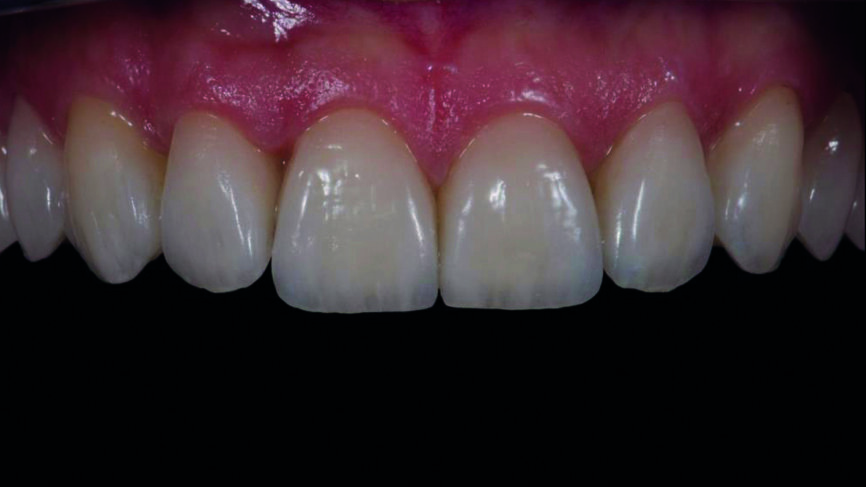

Fig. 17a : Résultat final une semaine plus tard.

Fig. 17b : Résultat final une semaine plus tard, vue de face

Le clinicien et la patiente ont décidé subjectivement un scellement des facettes en céramique feldspathique en raison des légères différences dans la longueur des incisives centrales des deux jeux. Les procédures adhésives ont suivi (Figs. 16a–f) et des photographies intra-orales et extraorales ont finalement été prises une semaine plus tard (Figs. 17a–e).

La prise d‘une empreinte intra-orale numérique est une autre procédure clinique qui s‘avère excellente par rapport à la technique d‘empreinte classique. Le plan de traitement numérique et le mock-up associé sont de puissants outils de communication à la disposition du chirurgien-dentiste, quoique l‘utilisation du logiciel exige des compétences particulières. Au regard du travail en laboratoire, mis à part les étapes de coloration et de glaçage, la plupart des techniques analogiques demandent plus de temps (fabrication des modèles positifs unitaires réfractaires, fabrication des facettes, ajustements) (Figs. 18a et b). Dans ce cas, le résultat esthétique des facettes en céramique feldspathique résultait d‘un choix subjectif mais le flux de travail analogique est beaucoup plus exigeant. Vu la réduction de la difficulté, de la vitesse, de la complexité et du désagrément causé au patient, l‘approche numérique est plutôt à privilégier (Figs. 18a et b).